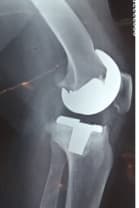

Үе дайрсан ясны анхдагч хавдар, ясны дутмагшлын үед хийгдэх мэс засалimg17Үе дайрсан ясны анхдагч хавдар, ясны дутмагшлын үед хийгдэх мэс засалimg18

Зураг 1. Сэргээн засах мэс заслын өмнөх рентген зураг. Эгц урд, хажуугаас авсан байдал.